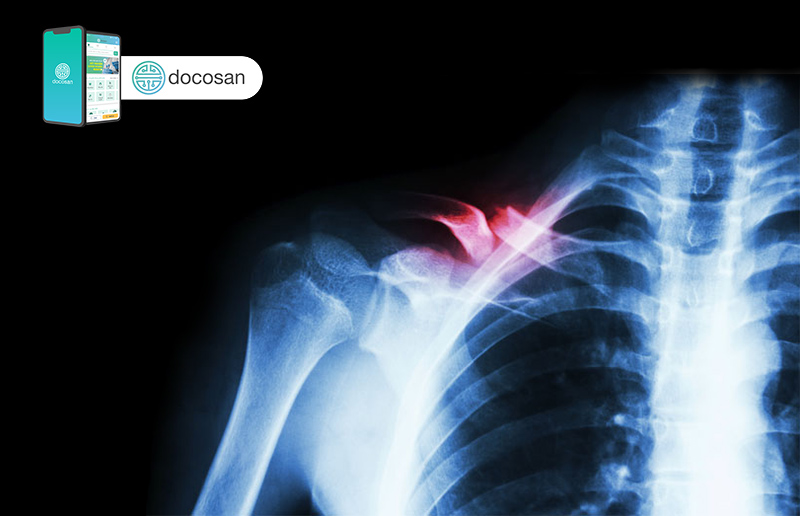

Bác sĩ sẽ cần làm thêm một số cận lâm sàng để đảm bảo rằng không có tổn thương thần kinh hay mạch máu kèm theo. X-quang là công cụ hình ảnh học đầu tiên được tiếp cận. X-quang xương đòn giúp xác định vị trí và mức độ của gãy xương. Có thể cần chụp thêm phim x-quang các xương khác của vùng vai. Nếu có kèm gãy xương khác, có thể bạn sẽ cần chụp cắt lớp vi tính (CT scan) để chấn thương được đánh giá chính xác hơn.